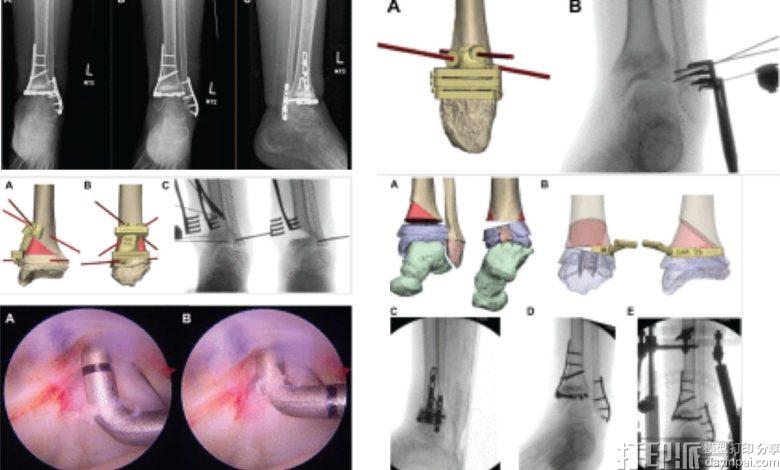

该团队开发了一个工作流程,将高分辨率CT扫描转换为数字3D模型,使外科医生能够在患者进入手术室之前虚拟规划和预演手术过程。我们最近报道了意大利一家医院的泌尿科团队如何成功使用类似过程来重建受肿瘤影响的肾脏。

一旦虚拟手术计划最终确定,工程师们便使用医用级3D打印机制造患者特异性器械。这些定制导板设计用于贴合特定患者的骨骼,并指导外科医生在哪里切割以及在哪里放置螺钉,从而减少对徒手技术的依赖。

作为案例研究,该论文记录了一名因罕见疾病导致严重胫骨下段畸形的13岁患者。标准手术方案需要融合踝关节,这一过程将严重限制患者的长期活动能力。

"相反,我们利用3D规划制定了一种保留关节的策略,"Frumberg解释道。"通过使用3D打印导板,我们能够重塑踝关节内部并恢复其自然对齐。结果,这位年轻患者恢复了活动能力,并重返他热爱的活动。"